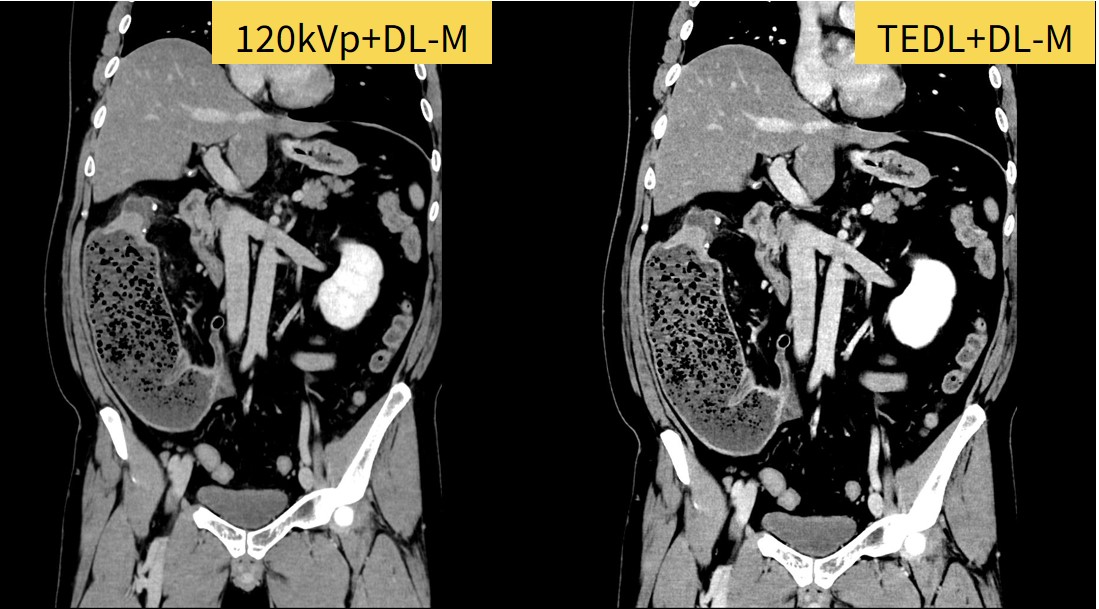

膵腫瘍・肝腫瘍疑いで紹介され精査のためDynamic CTを撮影。体重100kg、BMI34.7と高く、造影剤量が足りず本来の必要量の7割までしか注入できなかった症例です。

120kVpでも病変検出は可能ですが、TEDLを使用したことで正常部位とのコントラストが上昇し、視認性が上がり検出は120kVpよりも容易となっており、膵癌が十二指腸まで浸潤していることも分かりやすくなっています。また、TEDLを使用することでVR像の作成も十分に可能でした。

Fig7. 高体重症例で造影剤が不足した場合でも、TEDL・TFDLを用いることで

コントラスト、ノイズ低減で十分な画質が得られた症例